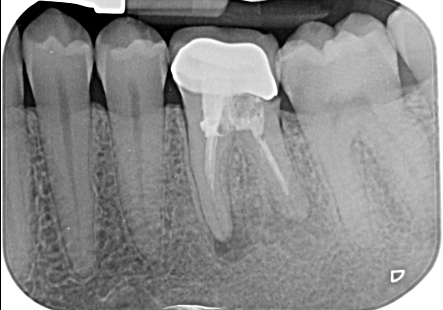

Il trattamento endodontico (devitalizzazione) consiste nel rimuovere la polpa dentaria o piu comunemente il nervo contenuto all’interno del dente e nelle sue radici, che sia infetto o infiammato.

L’obbiettivo di questa terapia è detergere, disinfettare e sigillare lo spazio lasciato libero dal nervo.

Attraverso l’esecuzione di una corretta terapia canalare si raggiunge l’obiettivo primario che è il mantenimento del dente, che dovra successivamente essere riabilitato protesicamente con corona o intarsio, all’interno del cavo orale scongiurando l’istaurarsi di infezioni e conseguentemente di dolore.